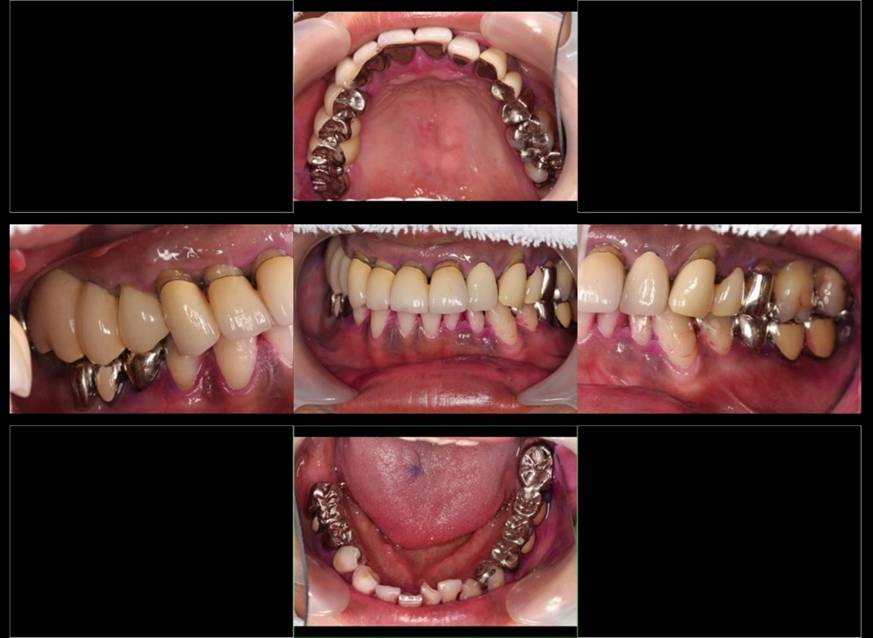

歯周病で抜歯せざるを得ず、インプラントを希望されたケース(使用インプラントはスプライン)

術前。すべての歯が歯周病の末期状態でブリッジ全体がうごいて噛めないとの訴え。右上の犬歯が腫れていました

術前パノラマレントゲン写真。根の周りが黒くなり、骨がなくなっていることがわかります

術後。上部構造はハイブリッドレジンです。しっかり嚙めるようになり喜んでいただきました。

治療後。歯周病で失われた骨が回復しています。使用インプラントはスプラインツイストです。

上部構造装着後6年。ハイブリッドレジンを使用したため、少し艶がなくなってきました。上部構造の材料には金属、ハイブリッドレジン、セラミックなどがあります。セラミックはきれいですが欠けやすいため、最近はフルジルコニアを使っています。